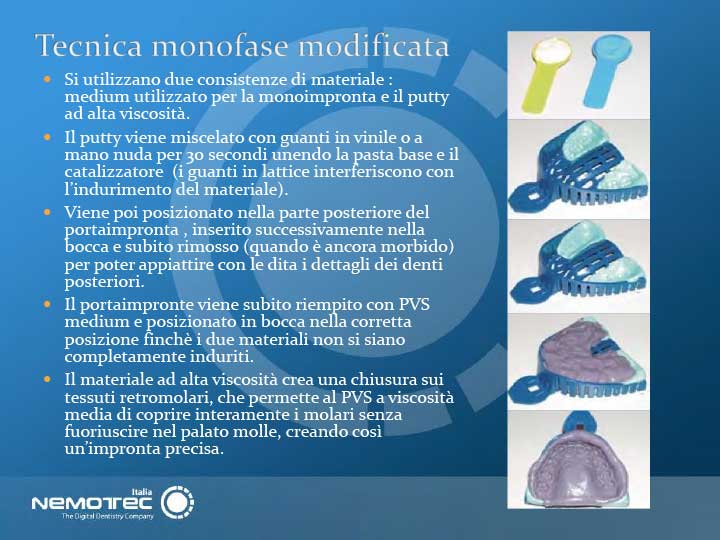

Siamo sicuri della nostra unicità, così come di quella che caratterizza i nostri clienti, in quanto ogni singolo specialista lavora in maniera diversa. Quello che realmente ci contraddistingue è la qualità dei nostri dispositivi, le esigenze cliniche e le tempistiche nell'esecuzione, ma soprattutto le peculiarità di ogni singola produzione. Ascoltiamo, capiamo, interpretiamo ma soprattutto sappiamo produrre dispositivi ortodontici di qualità, questo è quello che sappiamo fare meglio e lo facciamo insieme a Voi.

- Ortodonzia funzionale